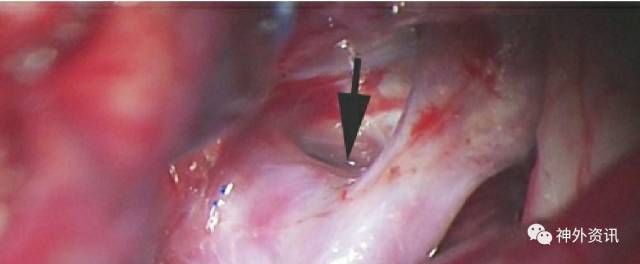

图17:PCoA的起始部往往只能看到一个小凸起,在动脉瘤囊正下方(见上方手绘图)。动脉瘤永久夹最终就是放置在这个小凸起(箭头,下图)和真正的动脉瘤颈之间。在接下来动脉瘤颈分离步骤中,通常需要应用临时阻断夹,尤其是对于破裂动脉瘤。